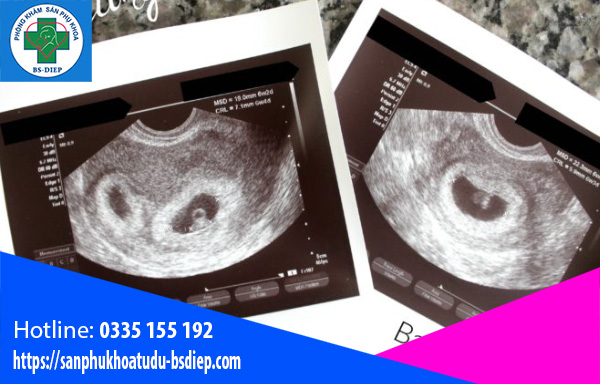

Ở tuần thứ 6 của thai kỳ, kích thước của em bé lúc này chỉ nhỏ cỡ bằng một hạt đậu. Nhìn em bé qua hình ảnh siêu âm thai 6 tuần có thể thất giống như một con nòng nọc có đuôi và cong hình chữ C.

Siêu âm đầu dò: Bác sĩ sẽ tiến hành đưa máy siêu âm có đầu tròn, dài qua ngã âm đạo. Hình ảnh siêu âm thai sẽ cho biết vị trí thai, kích thước, hình dạng của phôi thai. Mặc dù lúc này thai nhi nhìn sẽ chỉ giống như một đốm màu trên màn hình nhưng bác sĩ chuyên môn vẫn có thể đo được kích thước từ đầu đến mông.